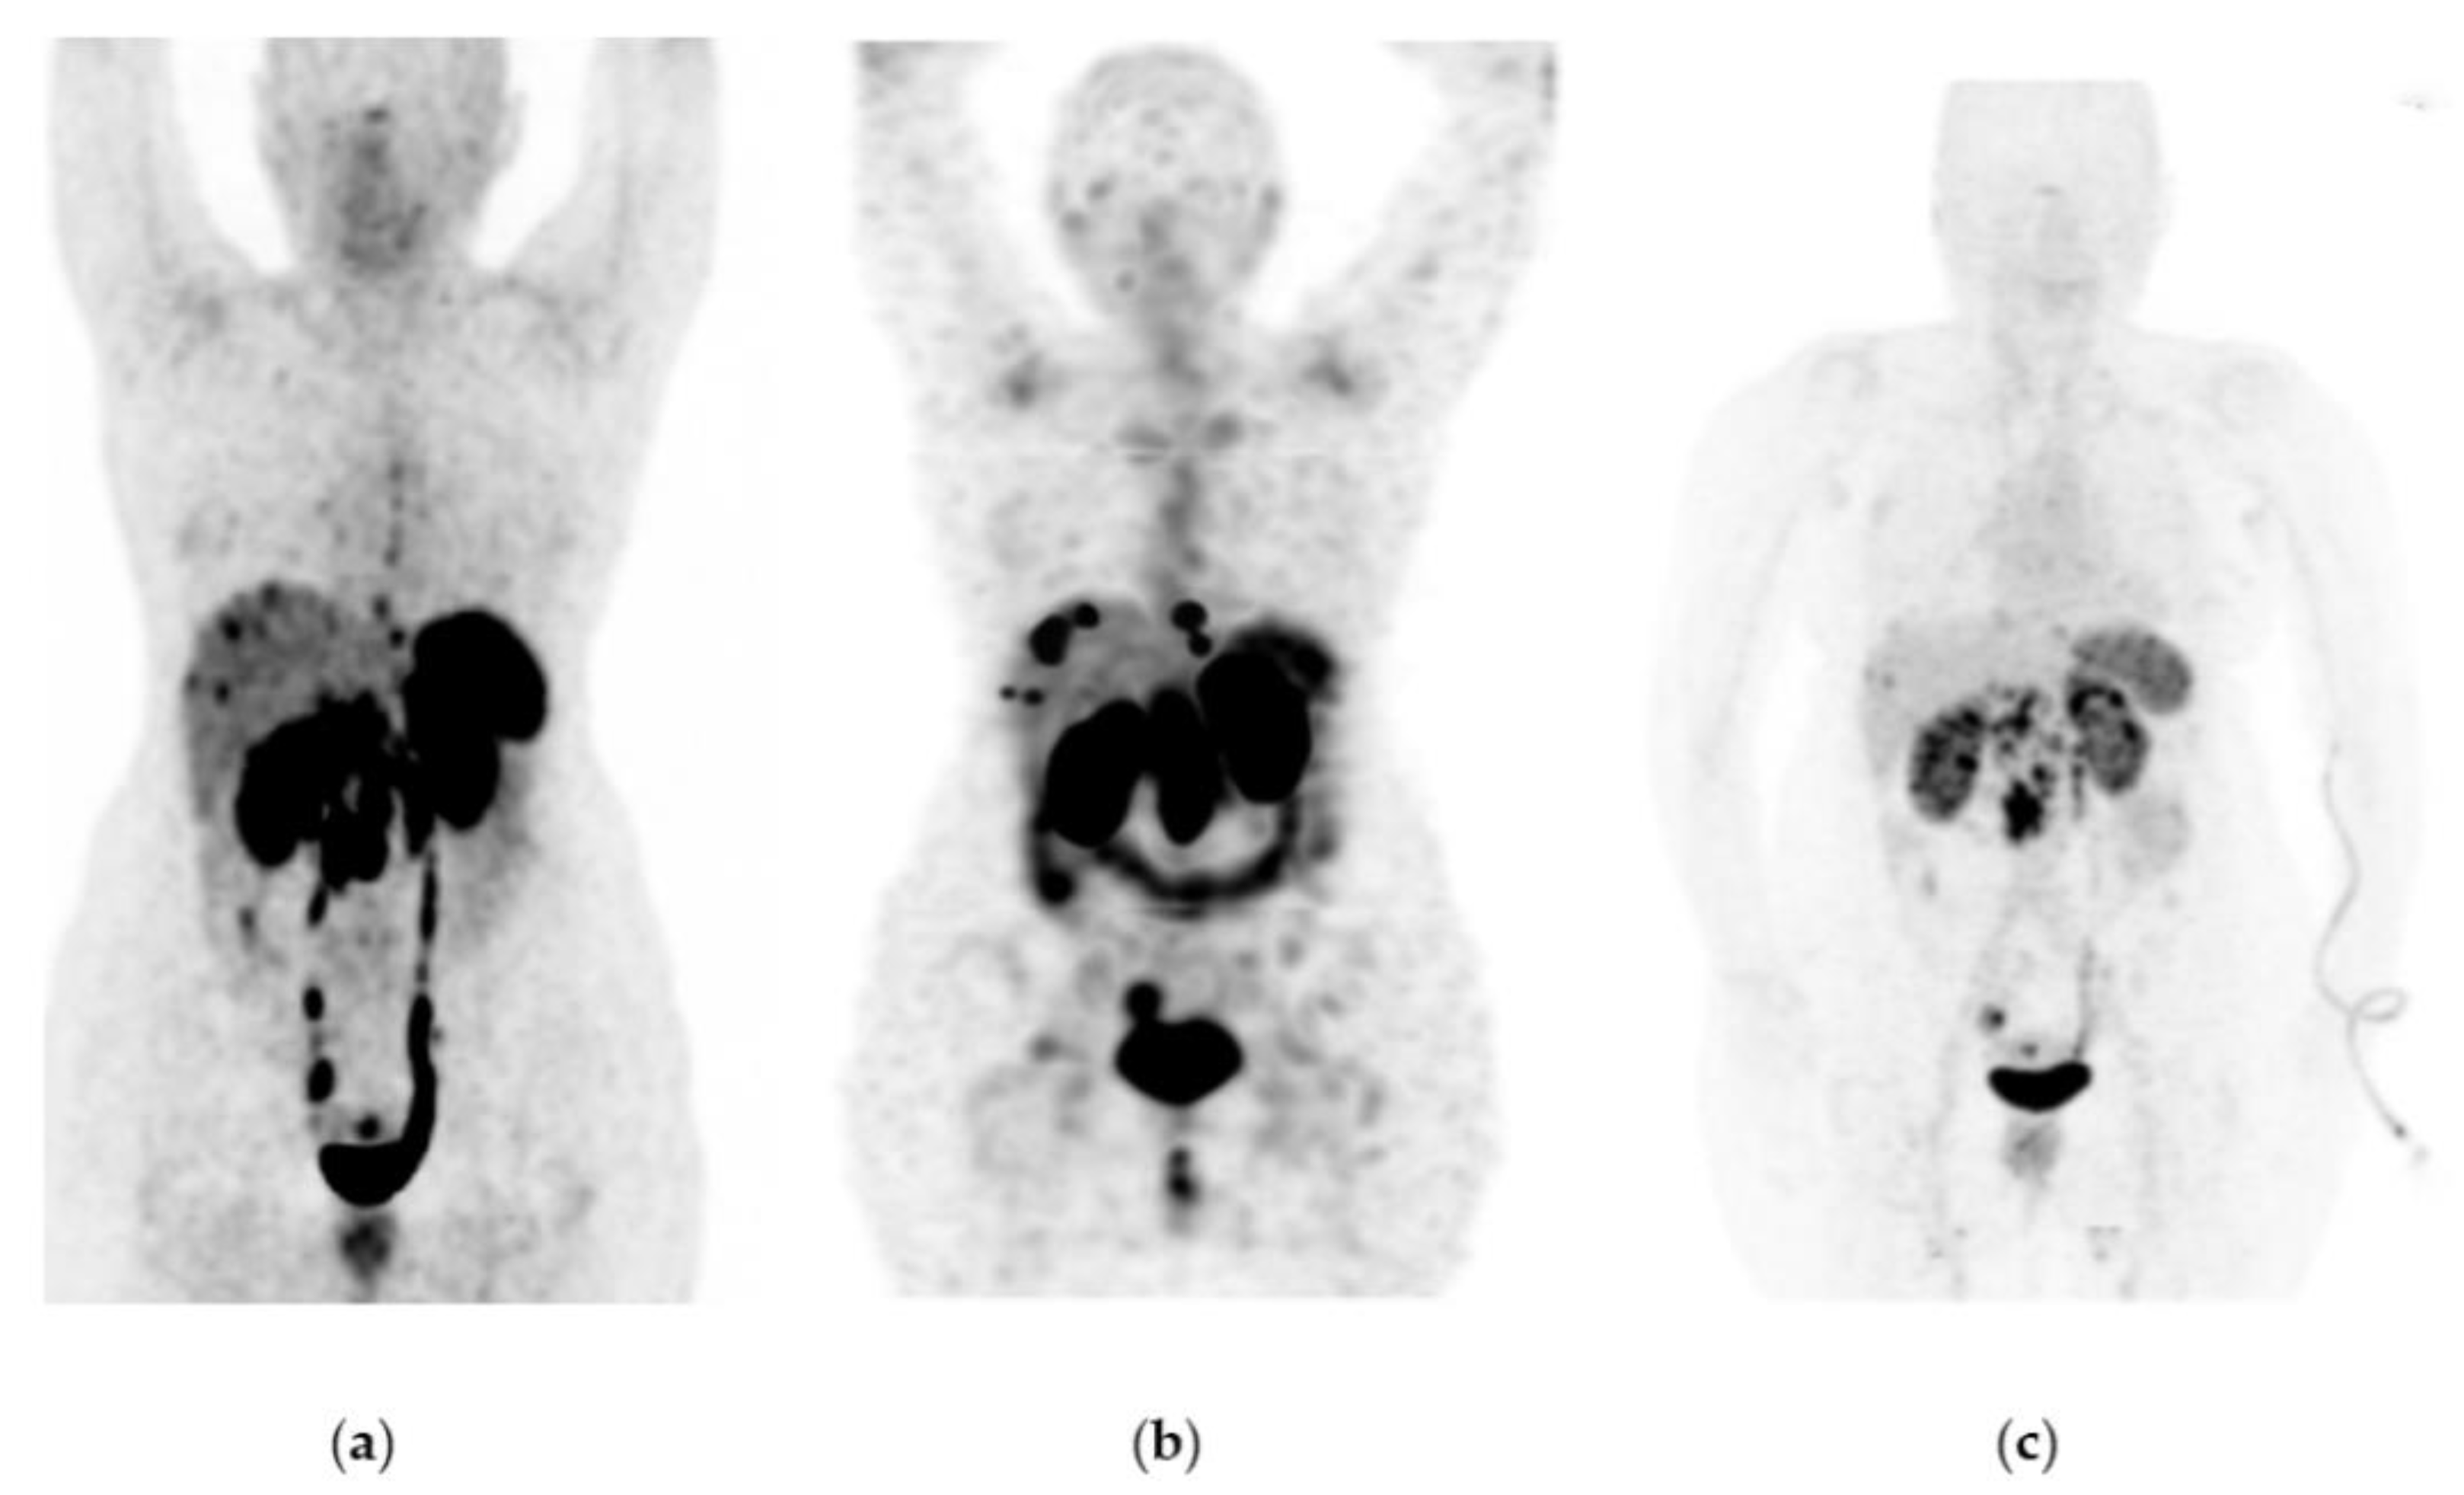

Figure 2. Patient with progressive and metastatic castration-resistant prostate cancer (mCRPC): (a) 68Ga-iPSMA PET/CT imaging before 177Lu-iPSMA therapy; initial levels of hemoglobin (15.5 g/dL), leucocytes (5700/µL), creatinine (0.82 mg/dL), platelets (238,000/µL), and serum PSA (129 ng/mL). (b) 177Lu-iPSMA SPECT imaging (first dose). (c) 68Ga-iPSMA PET/CT imaging eight months after the first 177Lu-iPSMA dose was administered; levels of hemoglobin (13.4 g/dL), leukocytes (3900/µL), creatinine (0.79 mg/dL), platelets (277,000/µL), and serum PSA (1.5 ng/mL). The patient responded completely to 177Lu-iPSMA therapy (four doses every six weeks; 7.4 GBq/dose).

177Lu-iPSMA showed an overall response rate of 36.6% (Table 2). Figure 2 and Figure 3 show typical clinical cases of complete response (disappearance of all lesions or adenopathies less than 10 mm short axis) and partial response (decrease of at least 30% in the sum of the largest diameters of lesions compared with the baseline study) after 177Lu-iPSMA therapy. In addition, the reduction of large tumors and multiple metastatic lesions are proof of the high specificity and molecular recognition of 177Lu iPSMA by PSMA at the tumor cell level (Appendix A) (Figure A1, Figure A2 and Figure A3).